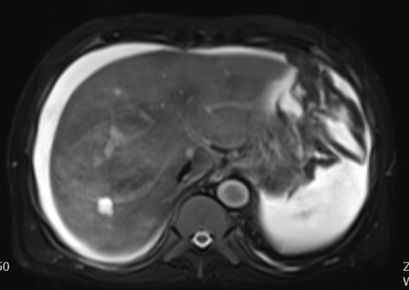

进一步检查及确诊:增强CT检查:下腔静脉肝段狭窄,内可见造影剂填充,肝脏异常强化(肝脏弥漫密度减低,门脉静脉期及平衡期显示肝脏不均匀强化,肝静脉周围呈片状明显强化,余肝实质呈轻度强化);腹部MRI:肝实质信号不均、肝静脉显示不清、腹水;肝脏病理活检:肝小叶结构未见异常,小叶中央为主的肝细胞片状退变坏死,灶性区域可见肝窦内淤血现象,形态提示缺血或淤血改变,致病因素包括药物/毒物、流出道梗阻(VOD、布加综合征)。免疫组化结果:CD34染色未见异常,CK7染色显示局部胆小管增生,局部肝细胞胆管化,HBsAg(-),特殊染色结果:Masson染色显示汇管区纤维组织增生,PAS、PAS+消化、铁、铜染色未见异常,网织纤维局部破坏。追问病史,患者起病前2月曾服用“三七粉”1月。最终诊断为吡咯生物碱相关性肝窦阻塞综合征。

MRI: